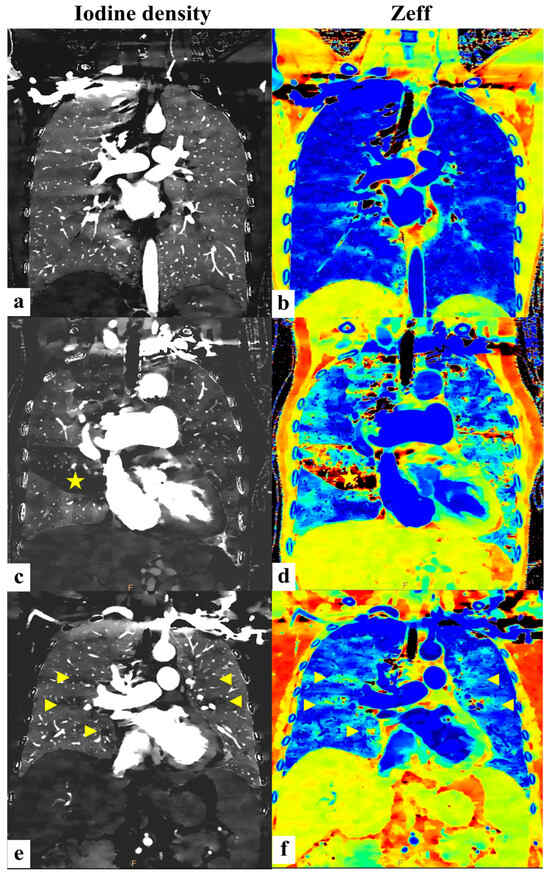

To further illustrate these findings graphically, Figure 5 displays coronal images comparing the iodine density and Zeff among the normal controls, PH patients, and CTEPH patients.

Figure 5.

(a,b) (normal controls): Bilateral lung parenchyma with uniform iodine density/Zeff demonstrating a homogeneous image pattern. (c,d) (CTEPH group): Patch region of lung parenchyma with decreased iodine density/Zeff (yellow asterisk) indicating an area with suspicious decreased pulmonary perfusion. (e,f) (non-CTEPH pulmonary hypertension group): Scattered small areas of diminished iodine density/Zeff (yellow arrowheads) interspersed among normal lung parenchyma, revealing a very heterogeneous pattern.